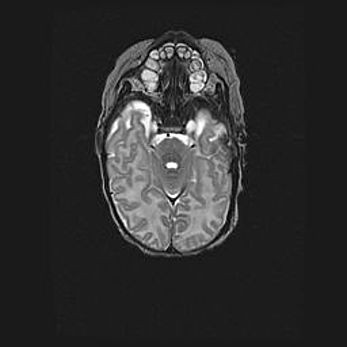

Церебральная ишемия II.

Возраст: 5 дней

Вес: 3400 г

Пол: женский

Окружность головы: 35 см

Срок гестации: 39 недель

Церебральная ишемия – это заболевание, характеризующееся недостаточностью (гипоксией) либо полным прекращением (аноксией) снабжения мозга кислородом по причине закупорки одного или нескольких сосудов. Это приводит к  что метаболическим расстройствам различной степени тяжести в тканях головного мозга, развитию коагуляционных некрозов и гибели нейронов.